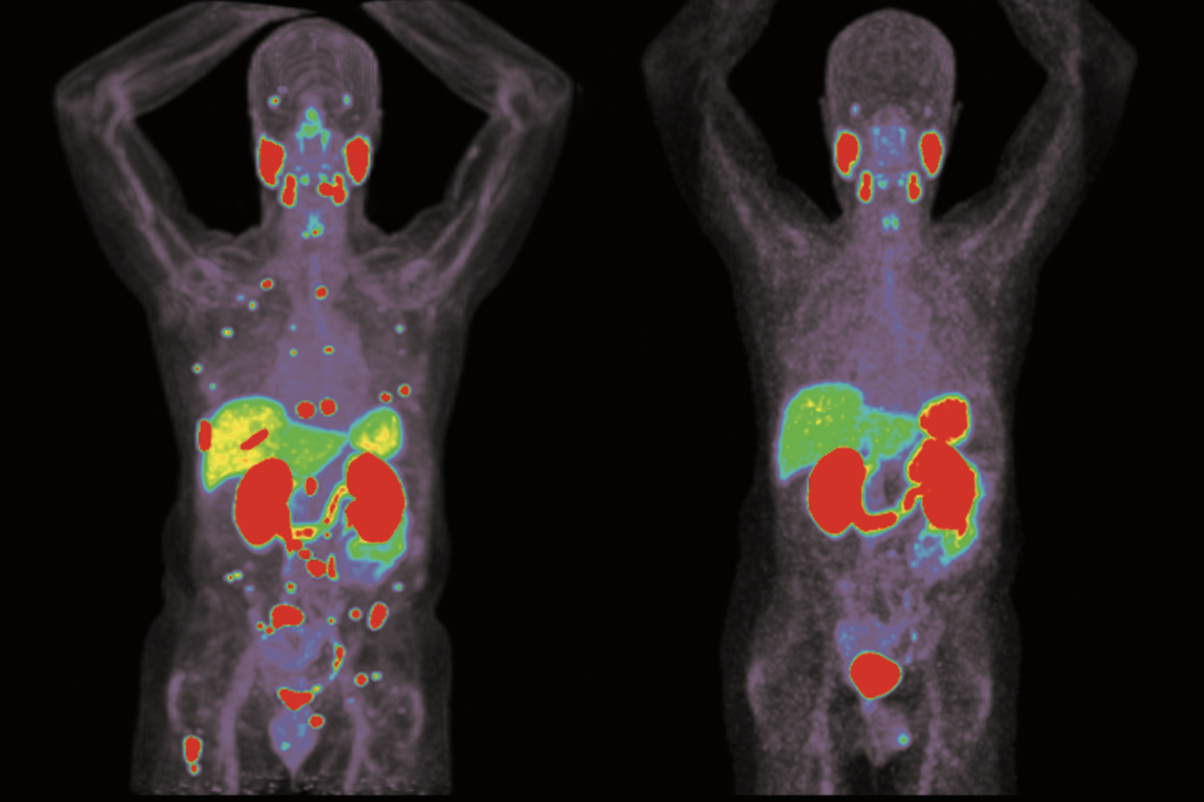

当 13 岁的足球少女 Anisa Juarez 被诊断出转移性乳头状甲状腺癌时,她的家人担心的不仅是生命的威胁,更害怕她不得不放弃最热爱的足球。不同于传统的放射性碘(RAI)治疗方案,UCLA Health 的医疗团队做出了大胆的决定——先使用 Selpercatinib(塞帕替尼),一种靶向 RET 突变 的抑制剂,以缩小肿瘤体积并增强其对 RAI 的反应性。

UCLA Health 的多学科团队为她量身定制了一份个体化治疗方案。在治疗癌症的同时,他们同样重视让 Anisa 能尽快回归活力与运动。医生采取了创新性的策略:先以 Selpercatinib 预处理肿瘤组织,使其对放射性碘更加敏感,再进行放射性碘治疗。这一顺序与传统方法相反,但效果显著——不仅大幅缩小了肿瘤负荷,也增强了 RAI 的摄取率,使治疗更精准,同时减少对健康组织的损伤。通过在治疗早期引入靶向药物,UCLA Health 正在重新定义儿童甲状腺癌的治疗模式。

UCLA Health 团队通过早期检测到 Anisa 的 RET 基因突变,率先使用 Selpercatinib,使治疗更精准、温和,有效降低了辐射负担。该方案对 RAI 不敏感或耐药 的肿瘤尤其具有潜力。通过先缩小肿瘤、提高 RAI 效果,Anisa 不仅避免了多次高强度放疗的副作用,也保留了生活质量与未来的健康潜能。

在 UCLA Health 的治疗下,Anisa 的病情改善显著。经过仅 5 个月的 Selpercatinib 治疗,她肺部结节明显缩小;血清甲状腺球蛋白(Thyroglobulin)水平从 23 ng/mL 降至不到 0.8 ng/mL(不到一年)。

更重要的是,她在治疗过程中未出现严重副作用,能够保持积极的生活状态,并重返足球赛场。这一成功案例表明,这种“先靶向、后放疗”的反向治疗策略,可能成为 RET 驱动型甲状腺癌 患儿的新标准方案。